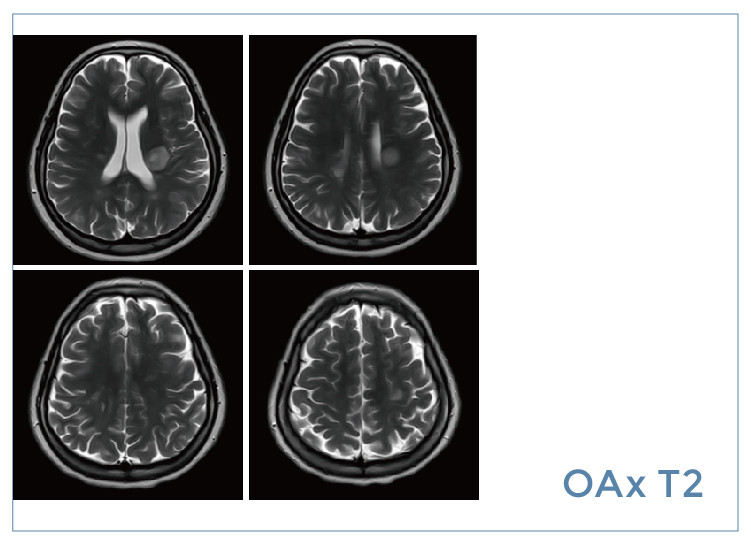

【朗润影像档案】20190830磁共振影像病例结果讨论